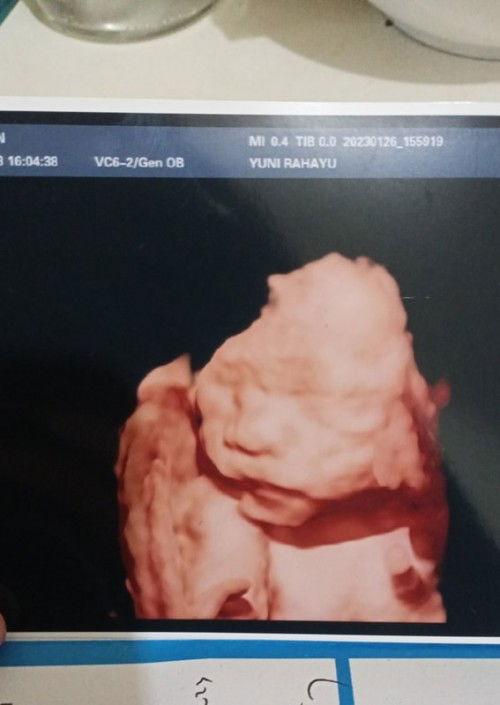

#seriusnanya bund disini ada pengalaman gk wktu usg jk cwok keluar cwek atau sebaliknya kmrin usg pas liat jknya 3d jk cwok masih berharap baby girl nih 😁